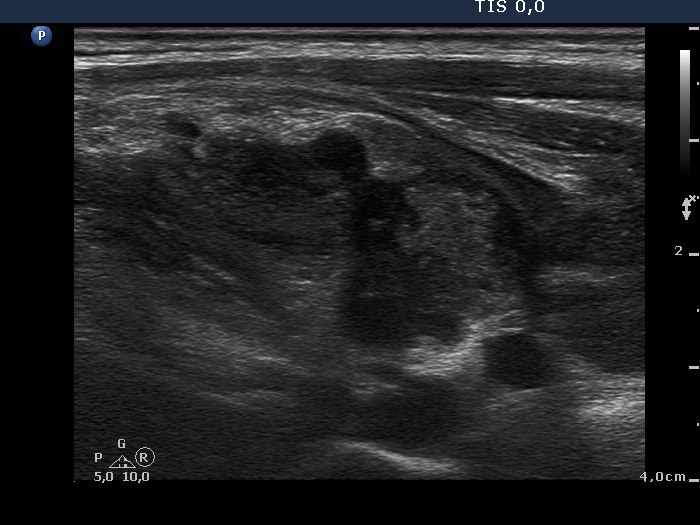

The mass in the left side of the neck corresponded to a conglomerate of multiple lymph nodes. These were irregular in shape and presented cystic and necrotic areas. There was no hilum present. The lymph nodes were avascular.